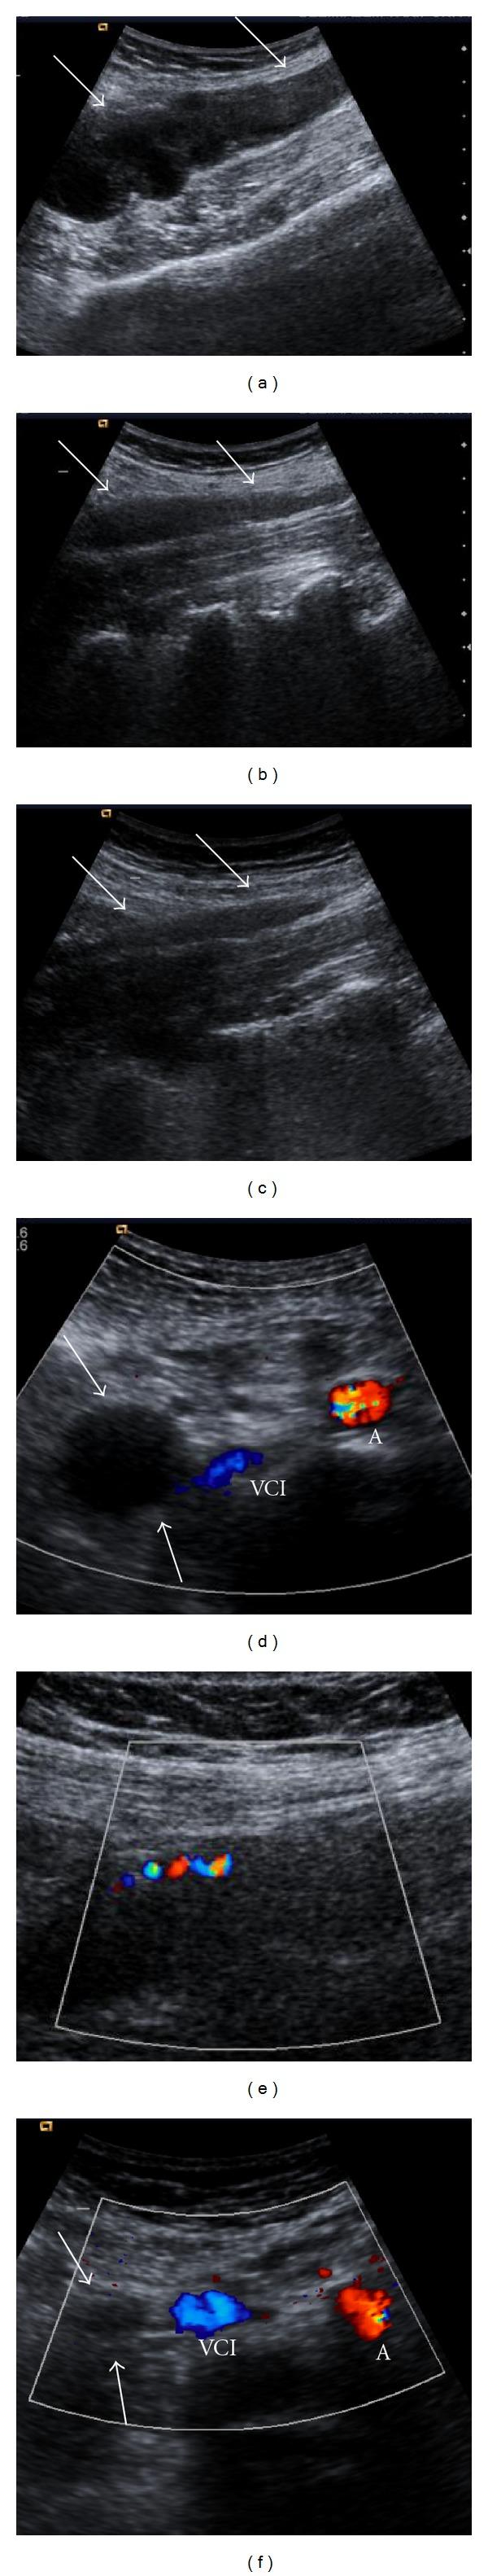

Postpartum ovarian vein thrombosis (OVT) is a rare but serious complication. Clinical findings of OVT are nonspecific. Postpartum OVT, which is a clinically difficultly diagnosed entity, must be thought of in differential diagnosis in cases of postpartum acute abdomen. OVT can be accurately diagnosed by appropriate noninvasive radiologic modalities to start early therapy with anticoagulants and intravenous antibiotics. In this paper, we review the imaging findings of a case with postpartum ovarian vein thrombosis that had been followed up for 6 months by ultrasonography (US), color Doppler US, computed tomography (CT), and magnetic resonance imaging (MRI).

产后卵巢静脉血栓形成(OVT)是一种罕见但严重的并发症。OVT的临床表现不具有特异性。产后OVT在临床上难以诊断,在产后急腹症的鉴别诊断中必须考虑到这一疾病。通过适当的非侵入性影像学检查手段可以准确诊断OVT,从而开始使用抗凝剂和静脉抗生素进行早期治疗。在本文中,我们回顾了一例产后卵巢静脉血栓形成患者的影像学表现,该患者通过超声检查(US)、彩色多普勒超声、计算机断层扫描(CT)和磁共振成像(MRI)进行了6个月的随访。